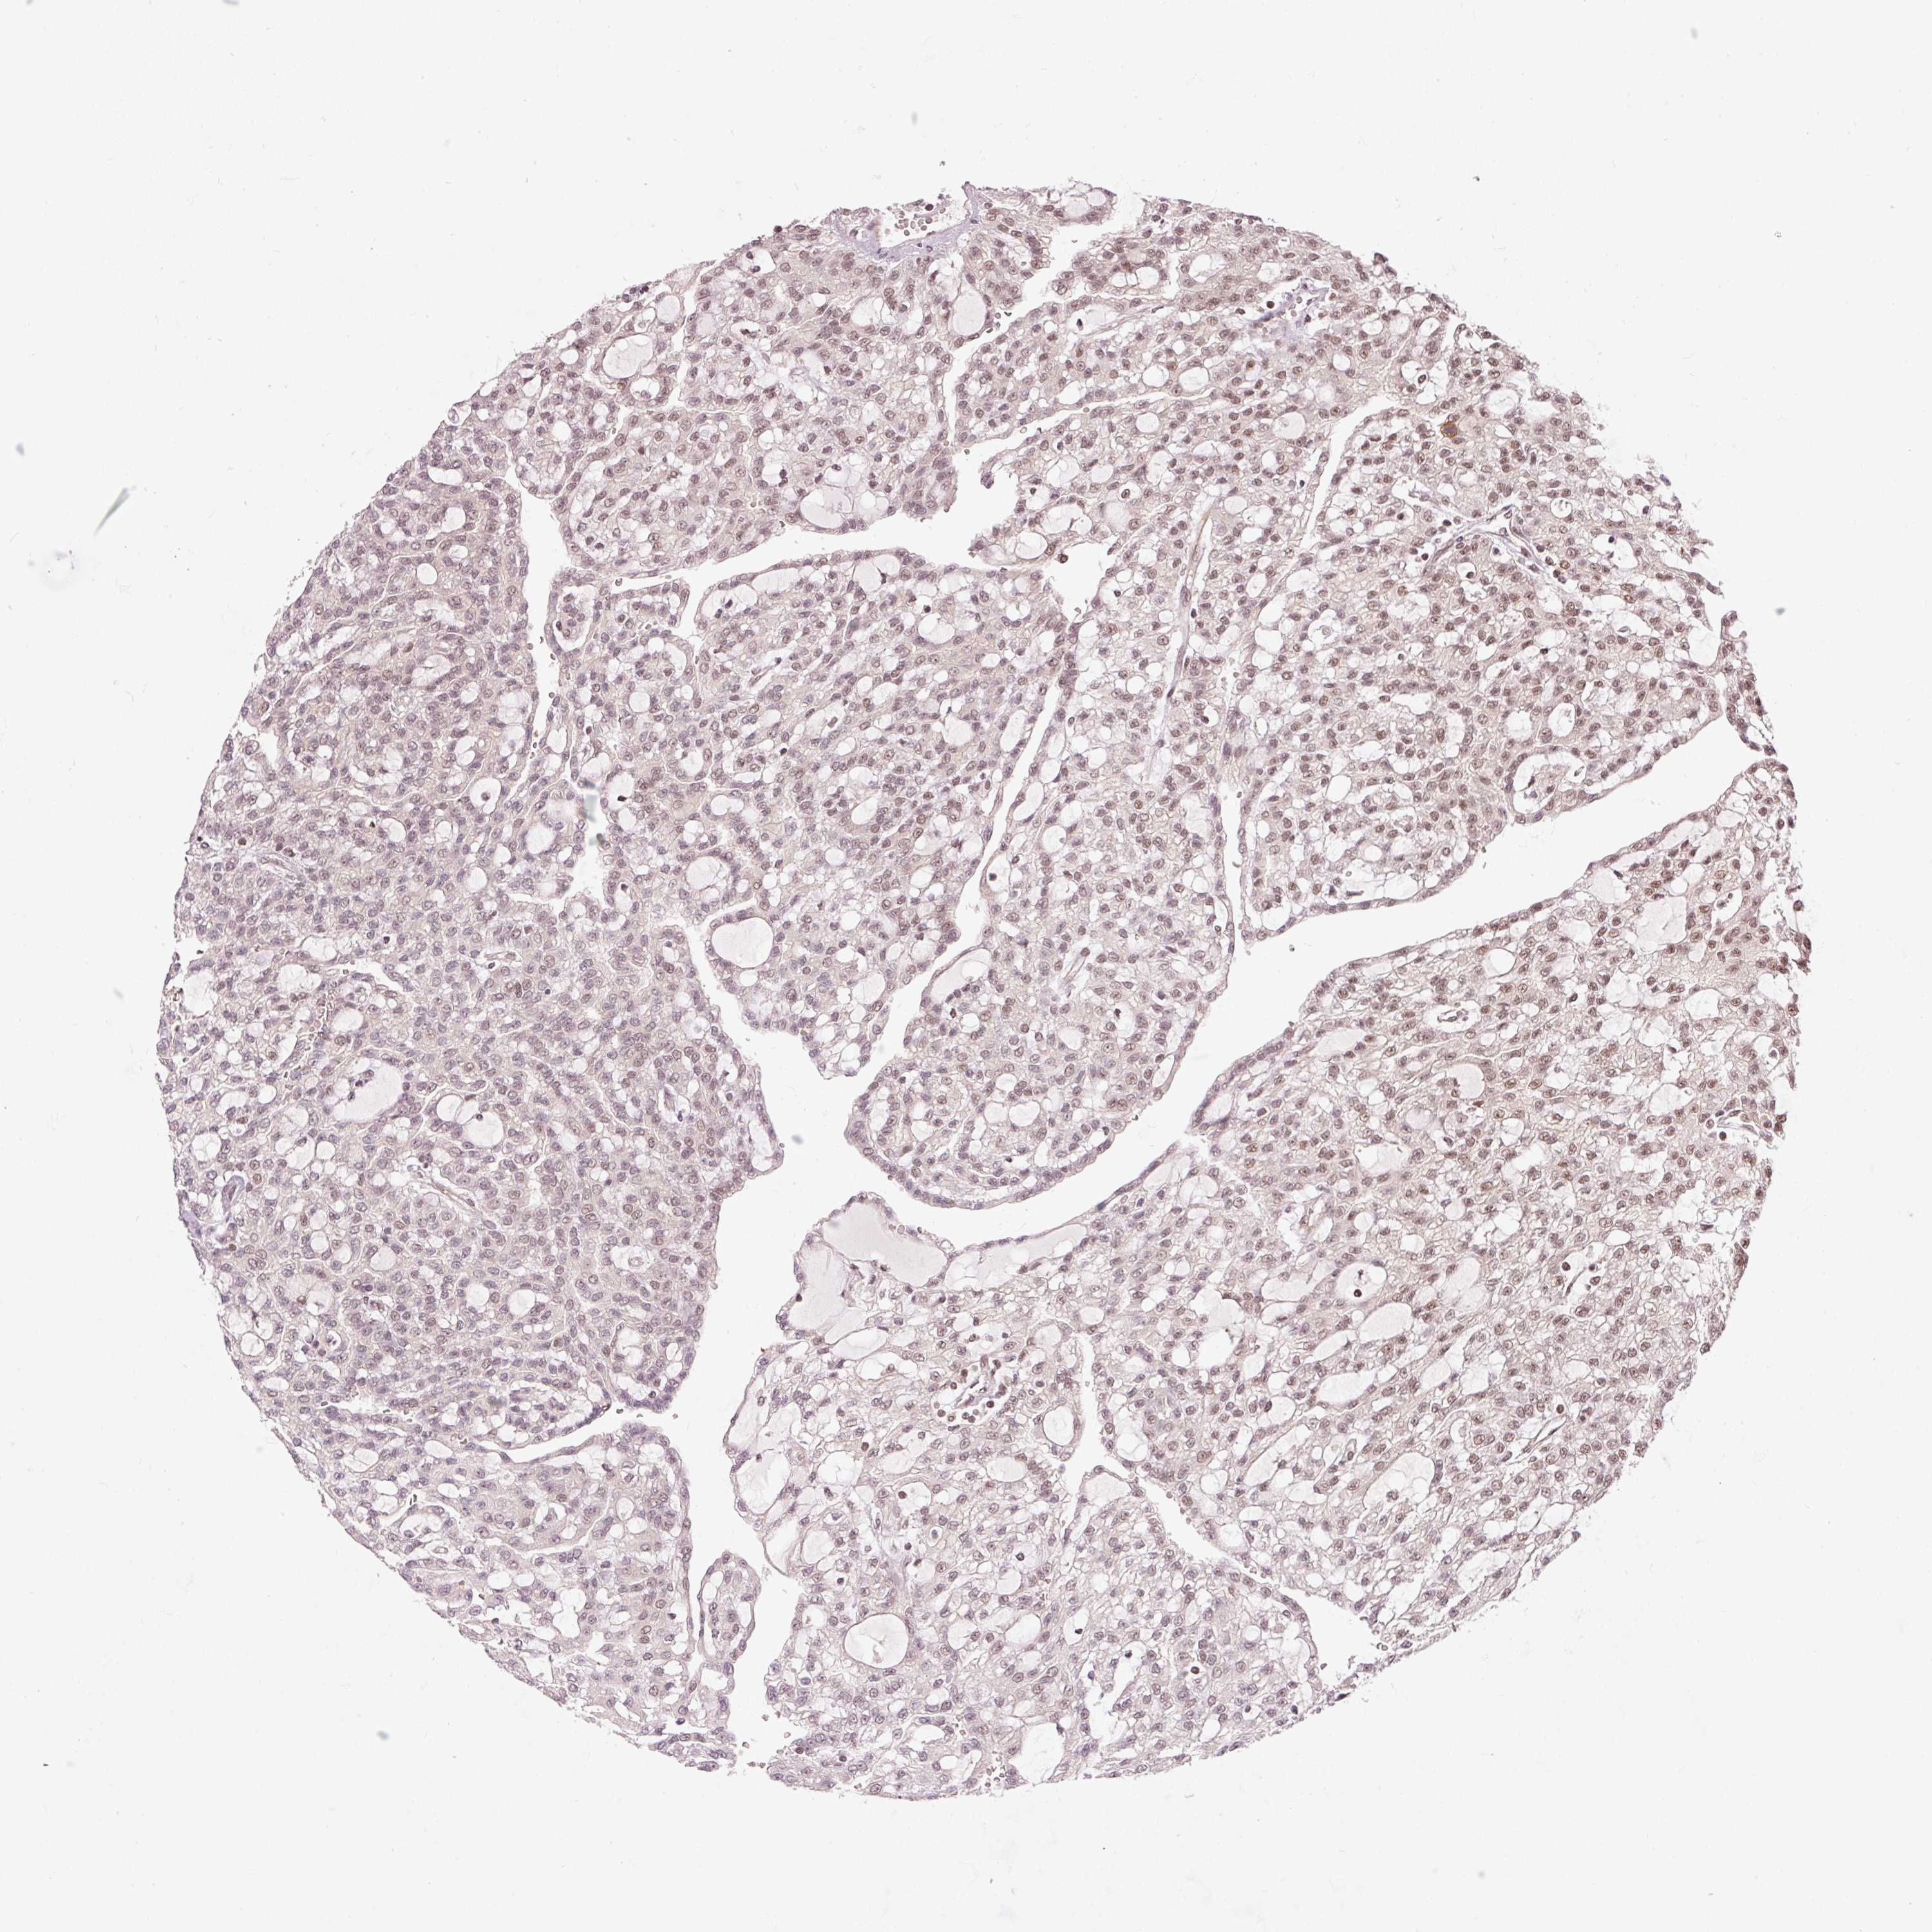

KIDNEY RENAL PAPILLARY CELL CARCINOMA (TCGA) - Interactive survival scatter ploti

The Survival Scatter plot shows the clinical status (i.e. dead or alive) for all individuals in the patient cohort, based on the same data that underlies the corresponding Kaplan-Meier plots. Patients that are alive at last time for follow-up are shown in blue and patients who have died during the study are shown in red.

The x-axis shows the expression levels (FPKM) of the investigated gene in the tumor tissue at the time of diagnosis. The y-axis shows the follow-up time after diagnosis (years). Both axes are complimented with kernel density curves demonstrating the data density over the axes. The top density plot shows the expression levels (FPKM) distribution among dead (red) and alive patients (blue). The right density plot shows the data density of the survived years of dead patients with high and low expression levels respectively, stratified using the cutoff indicated by the vertical dashed line through the Survival Scatter plot. This cutoff is automatically defined based on the FPKM cutoff that minimizes the p-score. The cutoff can be changed by dragging the vertical line or by entering a cutoff value in the square labeled "Current cut-off".

Under the Survival Scatter plot the p-score landscape (black curve; left axis) is shown together with dead median separation (red curve; right axis). Dead median separation is the difference in median mRNA expression between patients who have died with high and low expression, respectively. It is calculated as follows: median FPKM expression of dead patients with high expression - median FPKM expression of dead patients with low expression. This is intended to aid the user in visually exploring custom cutoffs and the associated p-scores and dead median separation.

Individual patient data is displayed and can be filtered by clicking on one or more of the category buttons on the top of the page. Categories describing expression level and patient information include: high, low, alive, dead, female, male and tumor stages. The scale of the x-axis can be toggled between linear and log-scale by clicking on the "x log" button. Mouse-over function shows TCGA ID, patient information and mRNA expression (FPKM) for each patient.

& Survival analysisi

Kaplan-Meier plots summarize results from analysis of correlation between mRNA expression level and patient survival. Patients were divided based on level of expression into one of the two groups "low" (under cut off) or "high" (over cut off). X-axis shows time for survival (years) and y-axis shows the probability of survival, where 1.0 corresponds to 100 percent.

THOC6 is not prognostic in Kidney Renal Papillary Cell Carcinoma (TCGA)

Best expression cut offi